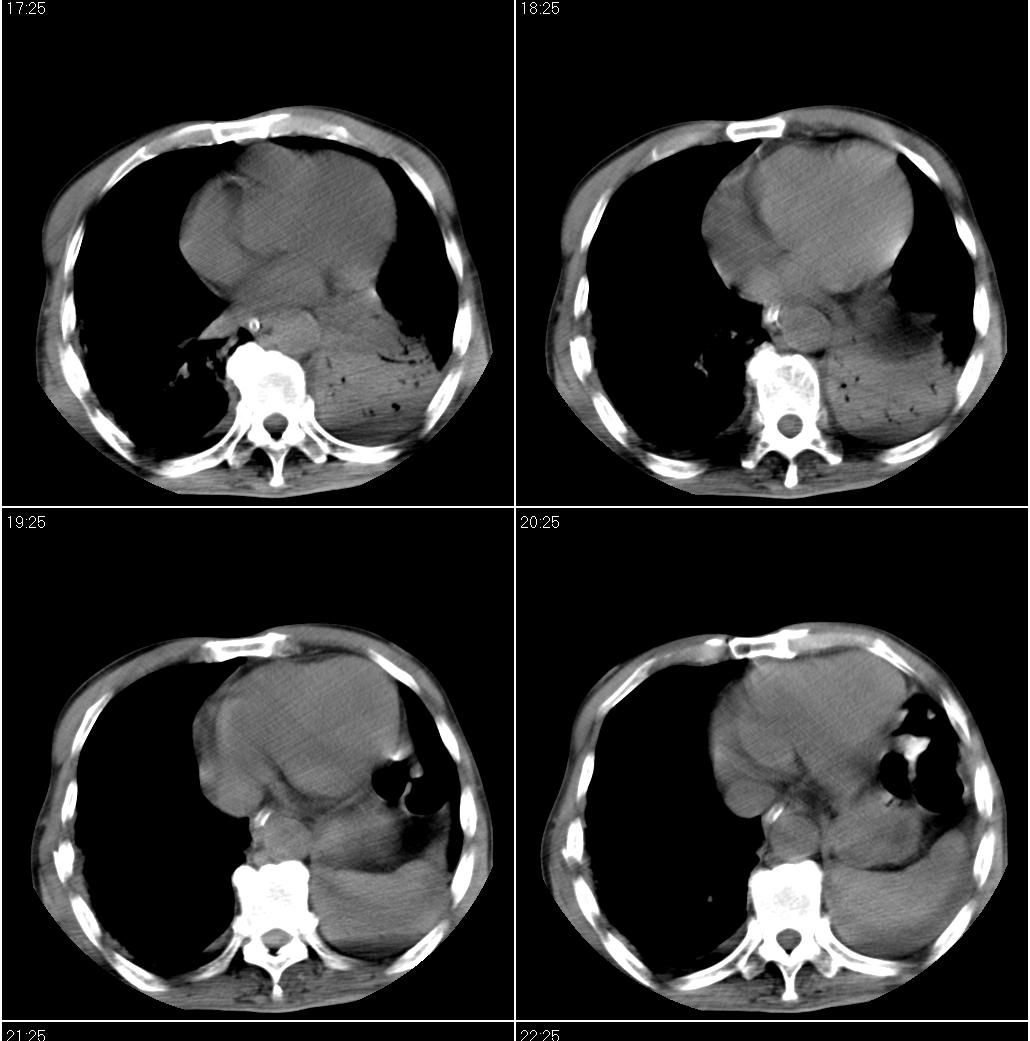

男性,65岁。因外伤来诊。该患者因脑外伤住院。以下是今天的dr和ct:

一周前胸片无异常,不考虑肿瘤,现x片及ct表现应与外伤有关,考虑左侧外伤性膈疝,并左下肺不张。右肺挫裂伤。少量胸水。

一周前胸片无异常,不考虑肿瘤,现x片及ct表现应与外伤有关,考虑左侧外伤性膈疝,并左下肺不张。右肺挫裂伤。少量胸水。支持

1 外伤性左侧膈疝、胸腔积液致左肺下叶不张 2右肺挫伤

右侧第7肋骨腋段骨折并右肺挫伤;左侧膈疝并肺不张。